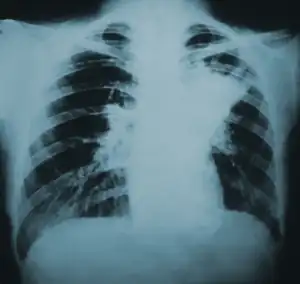

| Lung infiltration in blastomycosis. | |

Blastomycosis manifests as a primary lung infection in about 79% of cases.[8] The onset is relatively slow and symptoms are suggestive of bacterial pneumonia, often leading to initial treatment with antibacterials. Because the symptoms are variable and nonspecific, blastomycosis is often not even considered in differential diagnosis until antibacterial treatment has failed, unless there are known risk factors or skin lesions.[8] The disease may be misdiagnosed as a carcinoma, leading in some cases to surgical removal of the affected tissue.[19] Upper lung lobes are involved somewhat more frequently than lower lobes.[20] If untreated, many cases progress over a period of months to years to become disseminated blastomycosis.

Blastomycosis in the lungs may present a variety of symptoms, or no symptoms at all.[8] If symptoms are present they may range from mild pneumonia resembling a pneumococcal infection to acute respiratory distress syndrome (ARDS).[8] Common symptoms include fever, chills, headache, coughing, difficulty breathing, chest pain, and malaise.[8] Without treatment, cases may progress to chronic pneumonia or ARDS.[8]